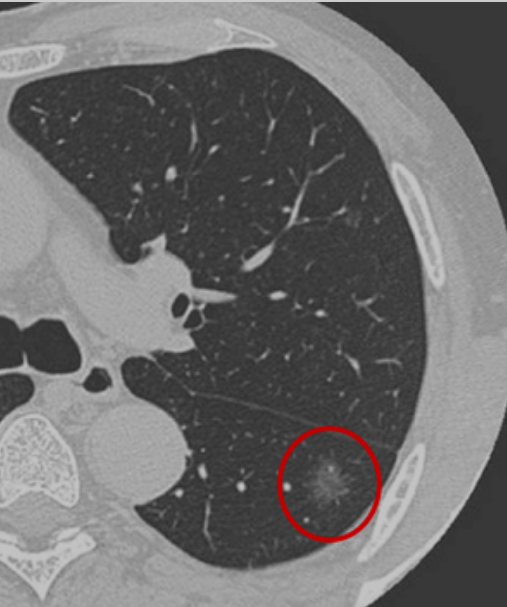

根据胸部CT判断是否存在磨玻璃密度成分,可将肺结节分为:纯磨玻璃结节、实性结节和部分实性结节。磨玻璃结节又叫磨玻璃影、毛玻璃结节等,表现为密度轻度增高的云雾状淡薄影或结节,在CT上跟磨砂玻璃一样。按病理性质,磨玻璃结节可以是良性病变如炎症或出血、局灶纤维化等,或者是癌前病变如原位腺癌、非典型腺瘤,也可以是恶性肿瘤如转移癌、微浸润腺癌等。

肺癌高危结节是指可能成为肺癌或转变为肺癌风险较高的肺结节,主要表现为直径≥1.5厘米或直径介于0.8至1.5厘米之间但表现出毛刺、分叶、胸膜牵拉、含气细支气管征和偏心厚壁空洞、空泡征等恶性CT征象的结节,以及直径大于0.8厘米的部分实性结节。此外,还需结合患者是否有肺癌家族史、长期吸烟史或患有其他恶性肿瘤病史等危险因素。高危结节通常需要经验丰富的影像科、肿瘤科、呼吸科或胸外科等医生进行综合判断。

目前在昆医大附二院肺结节MDT门诊中,有超过10%的患者都是肺多发结节,有的甚至超过5个,甚至更多。这需要进一步评估是晚期肺癌肺内转移?多原发肺癌?还是炎症引起,如果是多发磨玻璃应该引起重视。比如肺部体检发现3个多发结节,靠近胸膜有一结节大小1.5cm,且伴有实性成分、胸膜牵拉和可见毛刺,这就是威胁最大的病灶,也是我们首先需要处理的病灶,而左肺5mm、7mm结节相对比较稳定,可以继续密切随访,我们需要根据威胁最大的病灶选择最佳的治疗策略,因为其决定患者的预后。